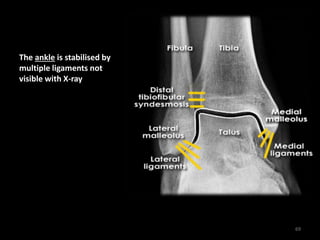

Ankle bone and ligament

anatomy

68

The ankle is stabilised by

multiple ligaments not

visible with X-ray